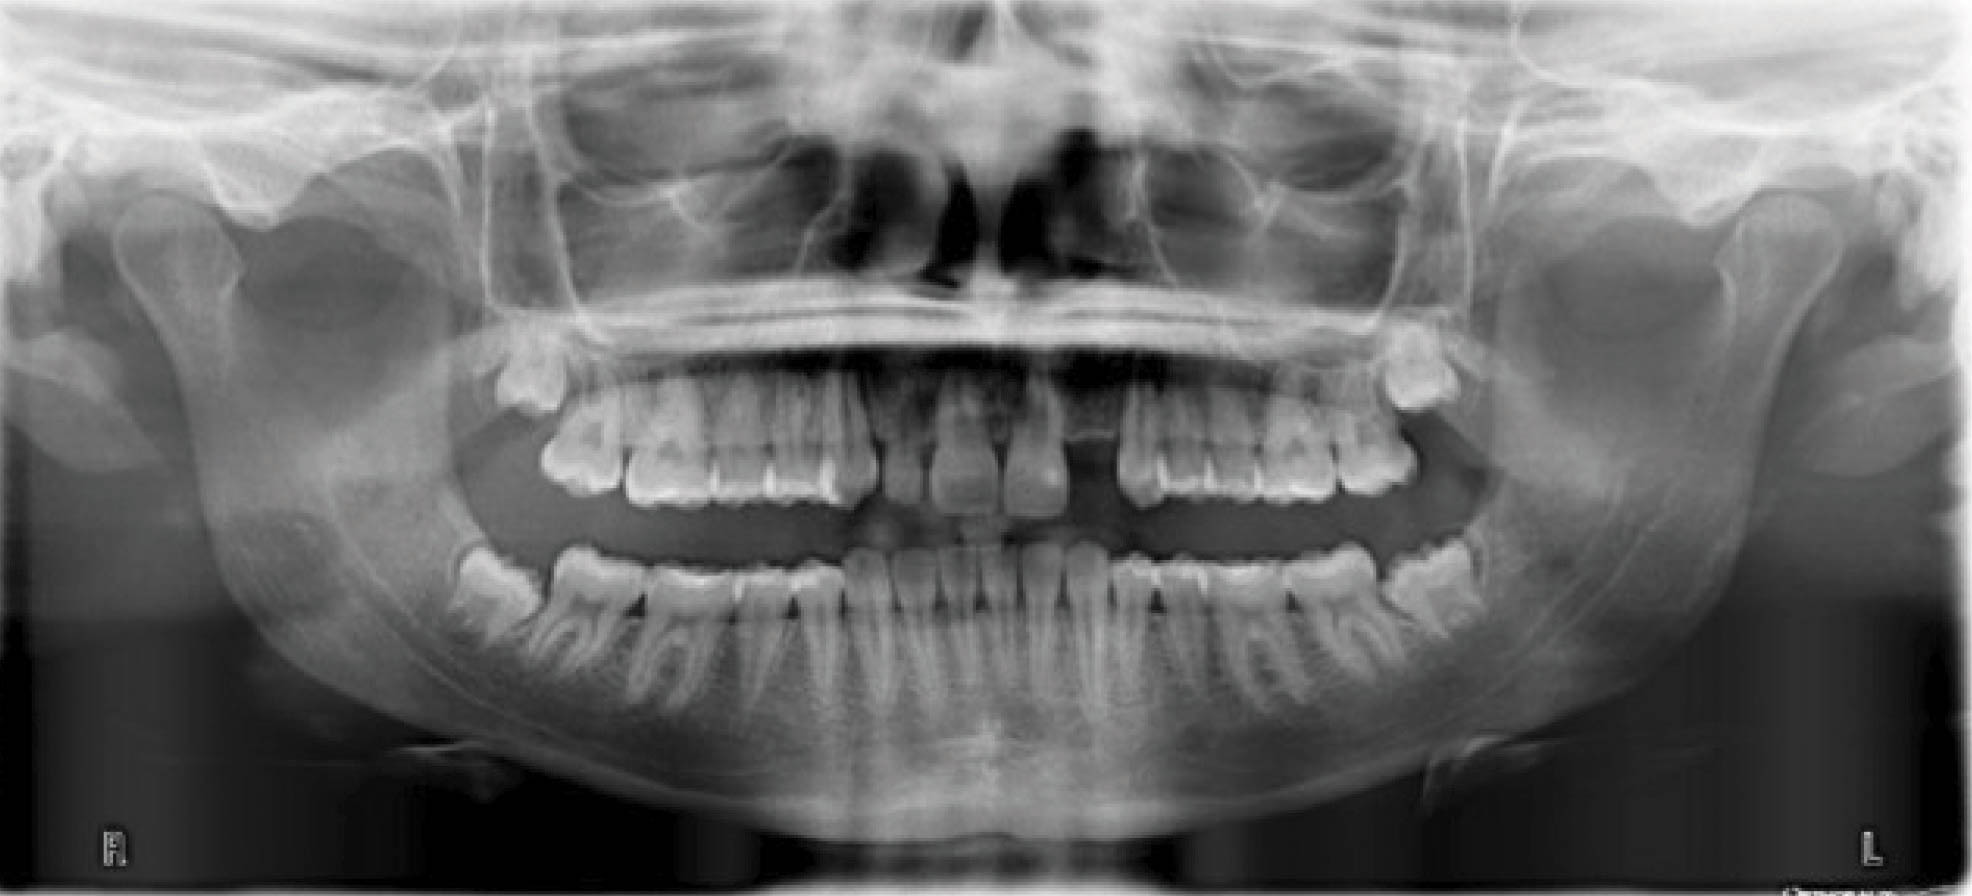

ده درجه تیپ اضافه و اگر فضا برای بستن داریم باید ۳۰ درجه تیپ اضافه در نظر بگیریم. به طور مثال در بیمار شکل 164-6 که لترال چپ بالا را ندارد، طرح درمان شامل دیستاله نمودن کانین چپ بالا تا رسیدن به اکلوژن است تا فضای کافی برای ایمپلنت لترال ایجاد شود. به دستوری که به لابراتوار داده شده نگاه کنید: لطفاً ریشه کانین چپ بالا را ۳۰ درجه بیشتر دیستالی کنید. چون نیرو، خارج از مرکز چرخش دندان و به تاج اعمال میشود، لذا باعث ایجاد تیپینگ میشود. در این بیمار اگر کانین چپ بالا را دیستاله کنیم چون بیشتر تاج دیستاله میشود، لذا در انتهای درمان ظاهر بیمار خیلی زشت میشود. از طرفی وضعیت ریشه آن هم به نحوی نیست که بشود برای لترال ایمپلنت قرار داد.

برای کانین چپ بالا درخواست ۳۰ درجه تیپ بیشتر میکنیم ولی انتظار رسیدن به چنین تیپی را نداریم. فقط میخواهیم که نیروی مناسبی روی کانین چپ بالا باشد تا حرکت ریشه هم داشته باشیم. شکل 165-6 یک سال بعد بیمار را نشان میدهد. همانطور که در عکس OPG میبینید حرکت بادیلی کانین چپ بالا رخ داده است. در واقع هنوز یک کمی ریشه مزیالی است که در قالبگیری جدید در خواست ۳۰ درجه زاویه بیشتر نمودیم. در ماه ۲۰ درمان فضا برای قرار دادن ایمپلنت آماده شده است (شکل 166-6).